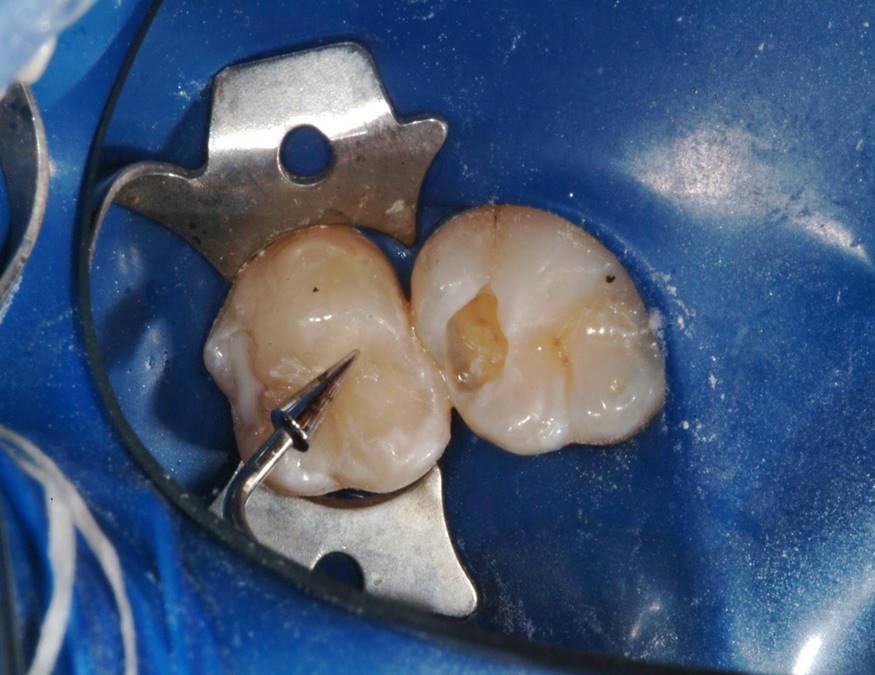

Fig 6. The amalgam restorations were thoroughly removed and the cavities prepared, after which caries indicator was applied to ensure the presence of only healthy, caries-free tooth structure.

Figure 6